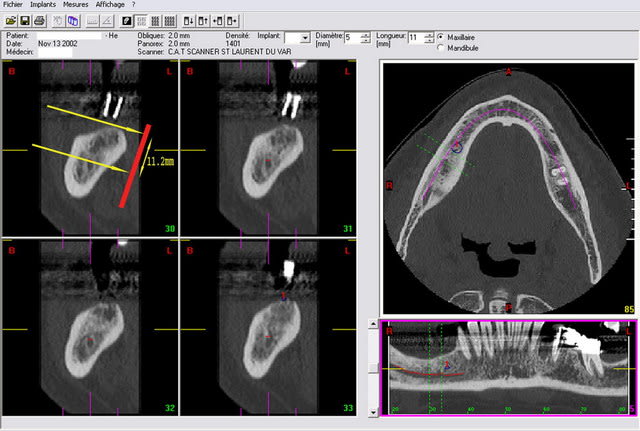

Je t'envoie 3 images de dentascan avec sur la premiere une "mesure" telle que tu l'aurais eu avec une retro-alveolaire sans deformation. On trouve 11,2 mm et une crete tres large favorable à un implant de diametre 5 mm et donc de longueur 1O ou 11 mm maxi.

Seconde image avec la simulation d'un implant de 11 mm... On est dedans ou alors on traverse la corticale linguale. Et encore ds cet exemple la corticale linguale ne fait pas un tres gros décroché comme on peut le voir parfois.